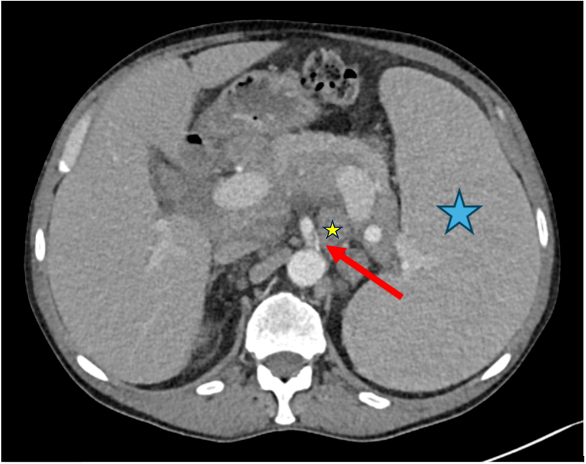

Figure 7.

Case 4, 66-year-old male with history of marginal zone lymphoma. A chest CT scan was performed after recovering from COVID-19 to assess post-primary changes in the lung. No pathological lung findings were observed. However, an incidental finding of a short dissection in the superior mesenteric artery was noted (red arrow). Additionally, the spleen (blue asterisk) and retroperitoneal lymph nodes (small yellow asterisk) are enlarged, consistent with the underlying disease.